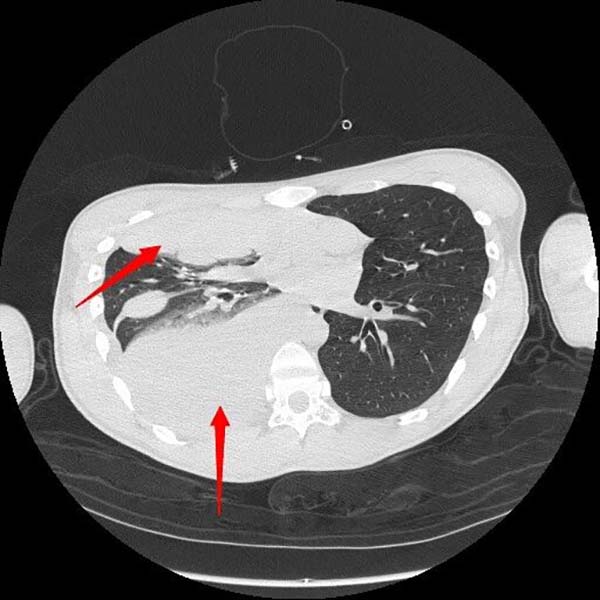

入院后胸部CT提示大量血胸,患者大汗、贫血貌,胸痛剧烈无法平卧。急诊第一时间联系胸外科会诊。胸外科主治医师赵云会诊后请示科主任崔健,明确右侧血胸诊断,决定立即手术治疗。医院麻醉科、第一手术区接到急诊手术通知后迅速响应,紧急做好术前准备。

手术由胸外科主任崔健、副主任医师胡晓丹,会同赵云,协同医院麻醉科、第一手术区手术室团队展开。术中胸腔镜下可见右侧胸腔大量血块,右侧胸顶存在活动性出血。由于患者此前已接受过两次胸腔手术,胸腔内创面组织情况复杂,再次止血难度较大。术中出血量累计达3000毫升,团队启用血液回收机进行血液置换并输血。